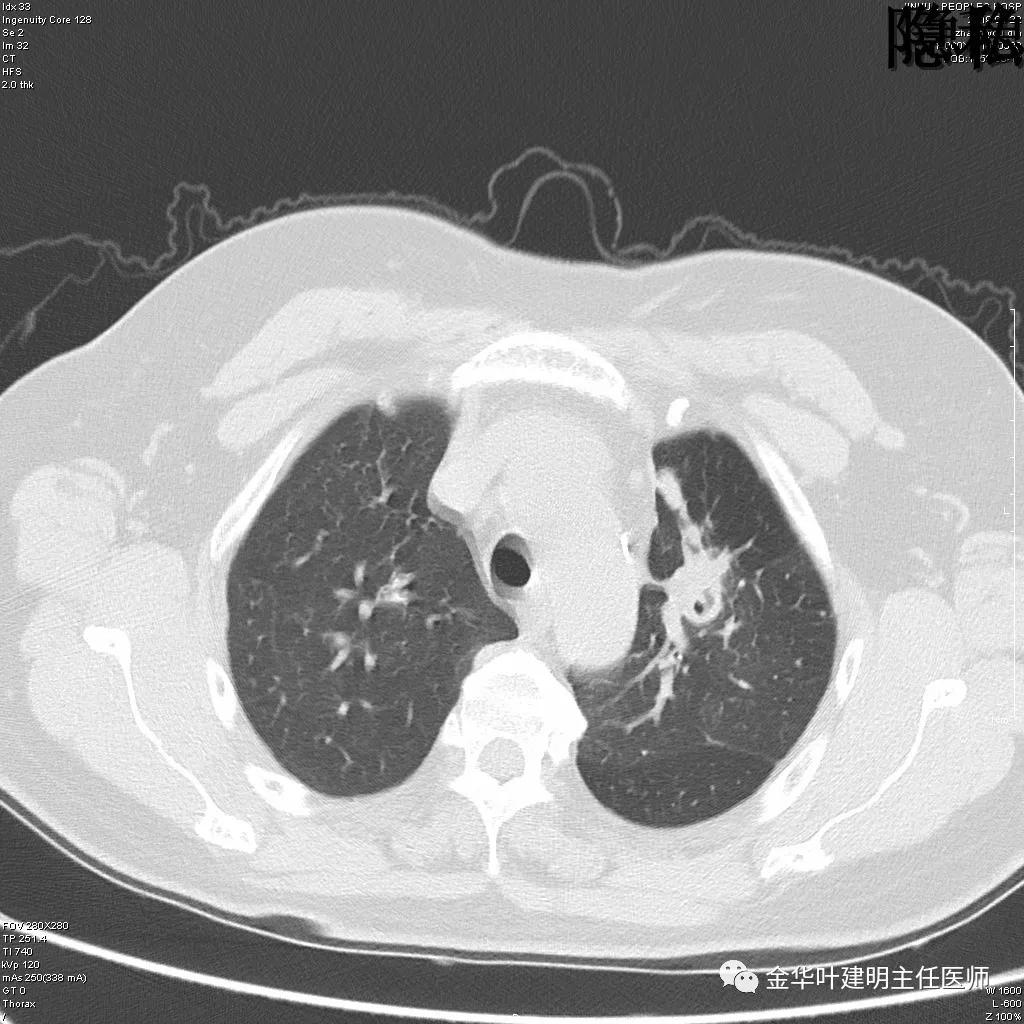

(病例资料2019年)金华的章某,今年60岁,前段时间因为咳嗽,到市区某三甲医院检查,发现她的左肺上叶与左肺下叶都有占位性病变。由于章某有亲戚在我们医院工作,所以在亲戚的指引下,让她来找我。我们予以适当的抗炎治疗,然后复发CT,发现病灶没有任何变化。其中平扫的片子如下:

可见左肺上叶有一占位,是空腔性的,其内有实性密度填充,是比较典型的肺曲菌病的表现,但病灶有点大,长径大于3-4厘米许。